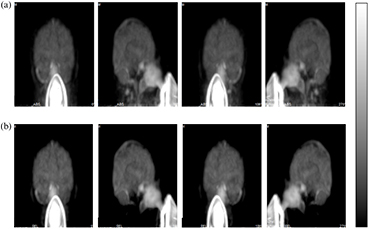

Standard image High-resolution imageFigure 5 shows comparison of the MIP calculated from PET images integrated over the initial 300 s after the start of the 60 s 15O2 inhalation, which were obtained from a healthy volunteer study. The two sets of images were with the scatter-correction procedures (a) that did not involve the outside-FOV scatter compensation and (b) that involved the outside-FOV scatter compensation. Regional radioactivity distribution is reasonable over the entire FOV when the outside-FOV scatter compensation was not involved. However, when the outside-FOV scatter correction procedures were applied to the reconstruction process, the carotid arterial regions were not visible. Also, part of the cerebellum and temporal lobe areas were missing. This is similar to the findings in the phantom experiments shown in figure 2. No clear differences were seen between the two procedures in the upper part of the cerebral regions.

Figure 5. Maximum intensity projection (MIP) images obtained from a healthy volunteer study during 15O2 inhalation. Image reconstruction involved the scatter correction with two different procedures. The upper row (a) represents images with the scatter correction, excluding outside-FOV scatter-compensation procedures and the lower row (b) represents images with the outside-FOV scatter compensation procedures.